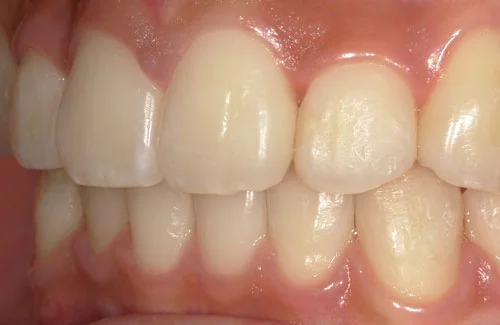

<症例7>歯がガタガタで噛み合わせが悪くお悩み

抜歯無し・マウスピースのみで矯正した症例です。

もともと歯列弓が非常に狭く、V字に近い形をしていたので噛み合わせも非常に不安定でした。

また、下顎前歯部がかなり上の方に生えていたため、下の前歯が上の前歯を突き上げてしまい出っ歯の状態になっていました。

現在では見た目はもちろん、臼歯の噛み合わせも改善しております。

奥歯の患者様も大喜びでした。

患者様と症状

主訴:歯のガタガタ、噛み合わせが悪い

性別・年齢:20代女性

問題点:叢生(重度)、V字歯列弓、ディープバイト

診断:前歯部の叢生を伴うアングルⅠ級、骨格性Ⅰ級の不正咬合

主なリスク:臼歯の移動に伴い一時的に咬合しにくくなる、歯肉退縮

症状:叢生(そうせい) 過蓋咬合(かがいこうごう)

治療内容

治療期間:1年10ヶ月

治療費用:990,000円(税込)

プラン:Full2プラン

抜歯:無し

再診治療費:無し

追加治療費:無し

保定装置費:無し

治療前後の写真